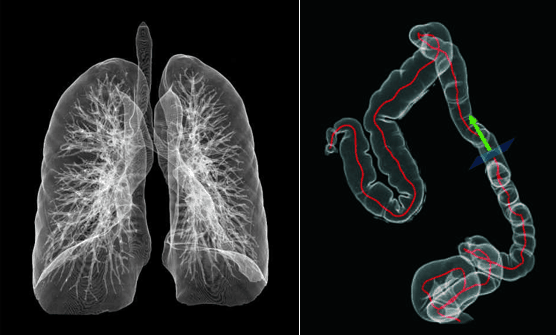

AccuOrgan-High resolution lung imaging.

High resolution images of the lung are obtained only by using 30 % – 40% of conventional radiation dose.

• Clinical Applications. Fast, precise and low-dose imaging provide a full range of clinical solutions to meet the current and future clinical diagnostic needs of the hospital.